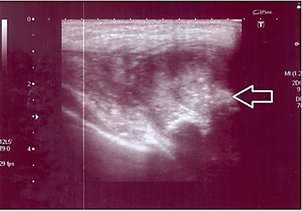

A seven-year-old boy was presented to us by his parents in our emergency department. The parents reported swelling of the young boy’s left shoulder/pectoralis muscle, which he had noticed after having fallen on it three weeks earlier but which he had not mentioned to them. Since the lump was becoming increasingly painful and the range of motion had reduced due to the pain, he told his parents about it after all and they then presented for consultation. Physical examination revealed a marked and pain-related reduction in range of motion of the left shoulder and arm, especially during abduction and elevation, as well as an obvious lump in the left pectoral area covered by stretched skin. Sonography was performed that showed a lesion of at least, 2.6 cm suggesting an organized haematoma. However, due to the size of the surrounding reactions, it was not entirely visible in sonography (Figure 1).

Figure 1: Soft tissue sonography of the left major pectoralis muscle: The linear probe cannot completely depict the extent of the lesion due to its size, making it necessary to use the curved probe with an imaging depth of 9 cm. An intramuscular lesion with a diameter of 2.6 cm, adjacent to the fascia and well distinguishable from other tissues, can be seen. It appears partly hyperechoic and partly hypoechoic compared to the surrounding muscle. The perfusion within the lesion is slightly increased.

There is only a little literature on intramuscular nodular fasciitis, such as in our case. The few existing reports state that this variant accounts for up to 10% of all findings in nodular fasciitis [1]. Not much is known on the pathogenesis of the disease. Assumptions have been made that there is an association to trauma (as in our case) [39]. The lesions can be detected easily in imaging. With ultrasound, they appear as well as distinguishable, mixed hyperechoic and hypoechoic lumps or masses (Figure 1) with slightly increased perfusion of the deep subcutaneous tissue adjacent to the fascia [39]. MRI cannot distinguish the various subtypes of nodular fasciitis such as myxoid, cellular or fibrous. Unfortunately, the morphology is very heterogenic and can mislead to the diagnosis of soft tissue sarcoma [40, 41]. When viewed in T1w sequences, lesions which are rich in cells are nearly isointense compared to musculature and hyperintense compared to fatty tissue in T2w sequences. Fibrous lesions however are hypointense in all sequences. Usually, the enhancement of contrast media is diffuse but can sometimes be located only peripherally (Figures 2 & 3) [42]. Biopsy is needed to confirm diagnosis in nearly every case. Genomic rearrangements of the USP6 locus are found in 92% (44 of 48) of nodular fasciitis [43]. Tomassen et al. recommended molecular analysis of untypical cases to avoid overtreatment due to misdiagnosis, which was previously described [3, 37].